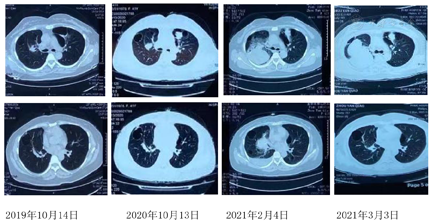

胸部CT(2018年11月19日):双肺多发囊性病变,右肺中叶囊性病变内可见结节状实变影(图1)

病程中间断复查胸部CT:右肺中叶切除术后,双肺多发囊性病变,右肺上叶可见一不规则结节状高密度影,并呈增大趋势,后于左肺上叶囊腔内出现新发结节状高密度影,病程中曾出现一过性右侧胸腔积液(图2)